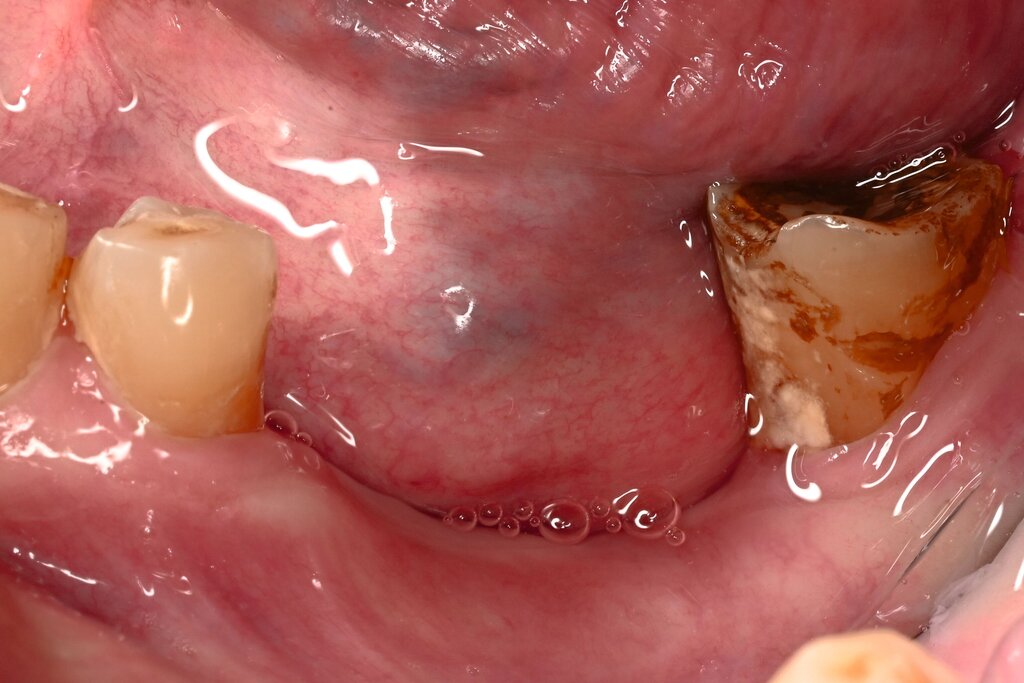

Der Patient stellte sich mit freiliegendem Knochen in Regio 43 bis 47 und mehreren gelockerten Zähnen vor. 45 und 46 waren devital. Als klinische Besonderheit fiel auf, dass sich innerhalb der Nekrosezone kleinflächige Weichgewebsareale darstellten, die in dieser Form bei klassischen Osteonekrosen üblicherweise nicht beobachtet werden. Eine klassische Vincent-Symptomatik bestand nicht. Drei Wochen zuvor war eine Herpes-Zoster-Infektion dermatologisch diagnostiziert und zunächst stationär behandelt worden. Der Patient erhielt eine intravenöse, antivirale Therapie, die bei Entlassung oralisiert wurde.

Zum Zeitpunkt der Erstvorstellung in der kieferchirurgischen Ambulanz zeigten sich keine klassischen Herpes-Zoster-Effloreszenzen im Gesicht. Eine antiresorptive Therapie oder Bestrahlung lag nicht vor, sodass eine Herpes-Zoster-assoziierte Osteonekrose im Sinne einer Ausschlussdiagnose festgestellt wurde. Anamnestisch bestand ein gut eingestellter Diabetes mellitus Typ 2 als potenziell immunkompromittierende Grunderkrankung. Die Knochenszintigrafie zeigte eine deutliche Stoffwechselsteigerung im betroffenen Bereich, vereinbar mit einer infizierten Osteonekrose.

Therapeutisch erfolgte eine gezielte Sequestrotomie und nur zwei Zahnentfernungen. Auf eine plastische Deckung wurde bewusst verzichtet. Stattdessen wurde Platelet-Rich Fibrin (PRF) auf die Wundfläche appliziert und mit einer Verbandplatte geschützt. Unter vorübergehender enteraler Ernährung über eine Magensonde zeigte sich eine nahezu vollständige Schleimhautregeneration innerhalb weniger Wochen. Eine kleine Restläsion in Regio 44 lingual heilte unter lokaler Therapie mit Chlorhexidin und einer Occlusivpaste vollständig ab. Eine Kontrollszintigrafie nach sechs Monaten bestätigte die weitgehende Ausheilung.